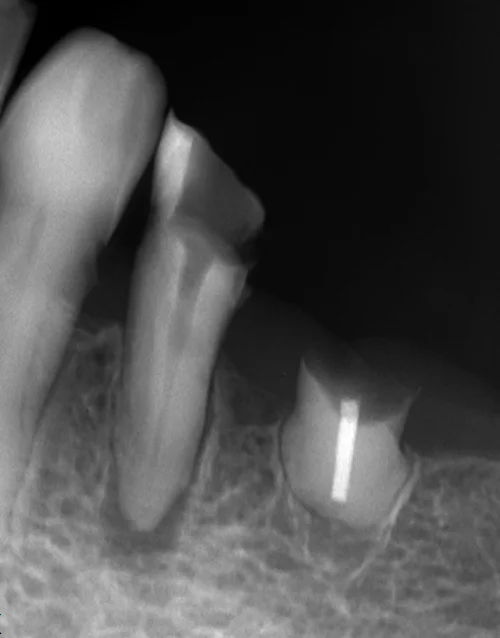

中心結節破折が原因で起こった神経の壊死を放置して、外部吸収が起こったケース

中心結節破折が原因で起こった神経の壊死を放置して、外部吸収が起こったケース